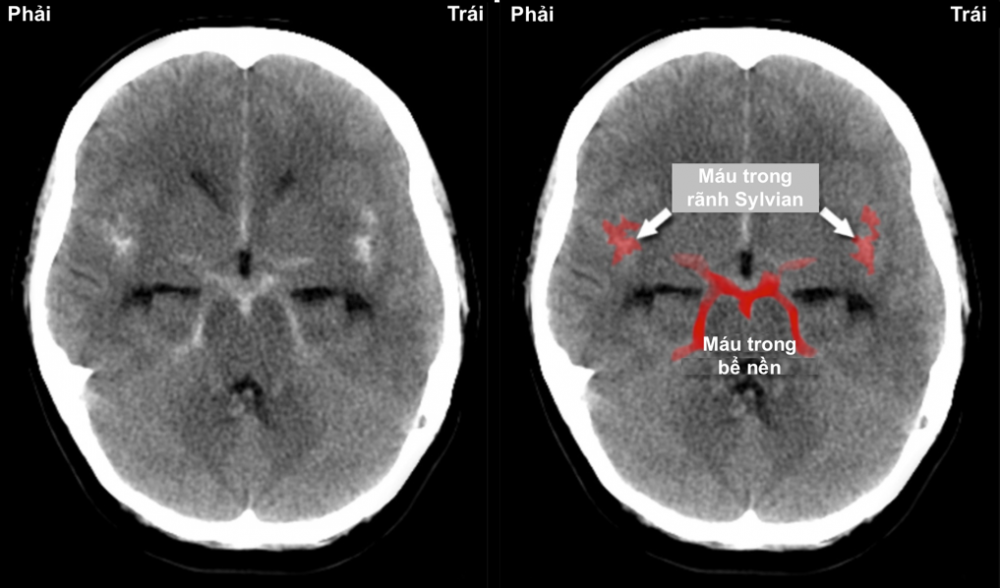

Hình 3. Hình ảnh cắt lớp vi tính sọ não sau chấn thương với xuất huyết dưới nhện trng rãnh Sylvian và bể nền (màu đỏ)

- CT scan não không cản quang: Là bước đầu tiên, có độ nhạy cao trong 6–12 giờ đầu sau khởi phát. Phát hiện máu trong khoang dưới nhện và xác định mức độ lan rộng.